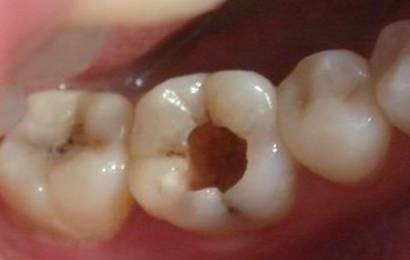

第二步中龋。

当您吃糖时,感觉酸疼,您说:“没关系,不是很疼。”牙医却说:“这时病变已经破坏到牙本质浅层了,牙齿已经有龋洞形成,对酸甜食物敏感,需要做填充治疗。”